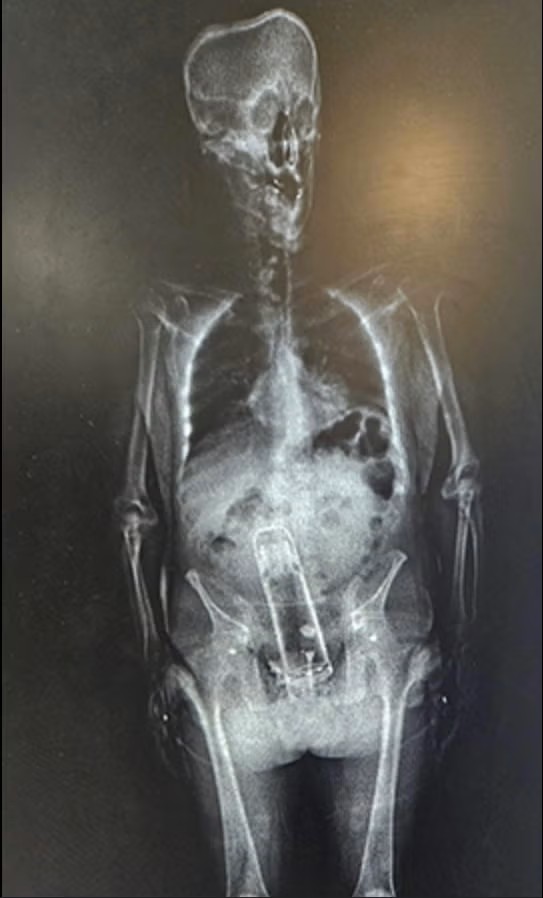

Sheriff Judd said Frymire was put through an X-ray scan to check for firearms and drugs, which led to a startling discovery.

“He brought a Thermus into the jail. That’s right. He put it up the exit ramp. You know what I mean?” Sheriff Judd says in the video while displaying a beverage container. “No, it wasn’t this one.”“He said, ‘well, I put that inside my body.’ And he didn’t swallow it 24 hours earlier.”

I ran that photo through one of those AI image describers hoping that it could help me with some good alt text or otherwise give me some kind of inspiration for where to take this post other than the obvious places, such as the hospital to which Frymire had to be taken in order to undergo a removal procedure. He’ll be ok, best I can tell.

But anyway, I asked the thing twice, and it swears that what’s stuck in there appears to be a mobile phone. I’ve used plenty of thermoses and mobile phones in my time, and I’ve never seen one that looks like the other. So how smart is this AI stuff, really? Like you’re seriously going to tell me that they train these models by sweeping up the entire contents of the internet and yet none of them are experts in what’s up someone’s ass? That’s literally what half the internet exists for. Colour me unimpressed. With the AI, at least. I find myself strangely awed by Mr. Frymire.